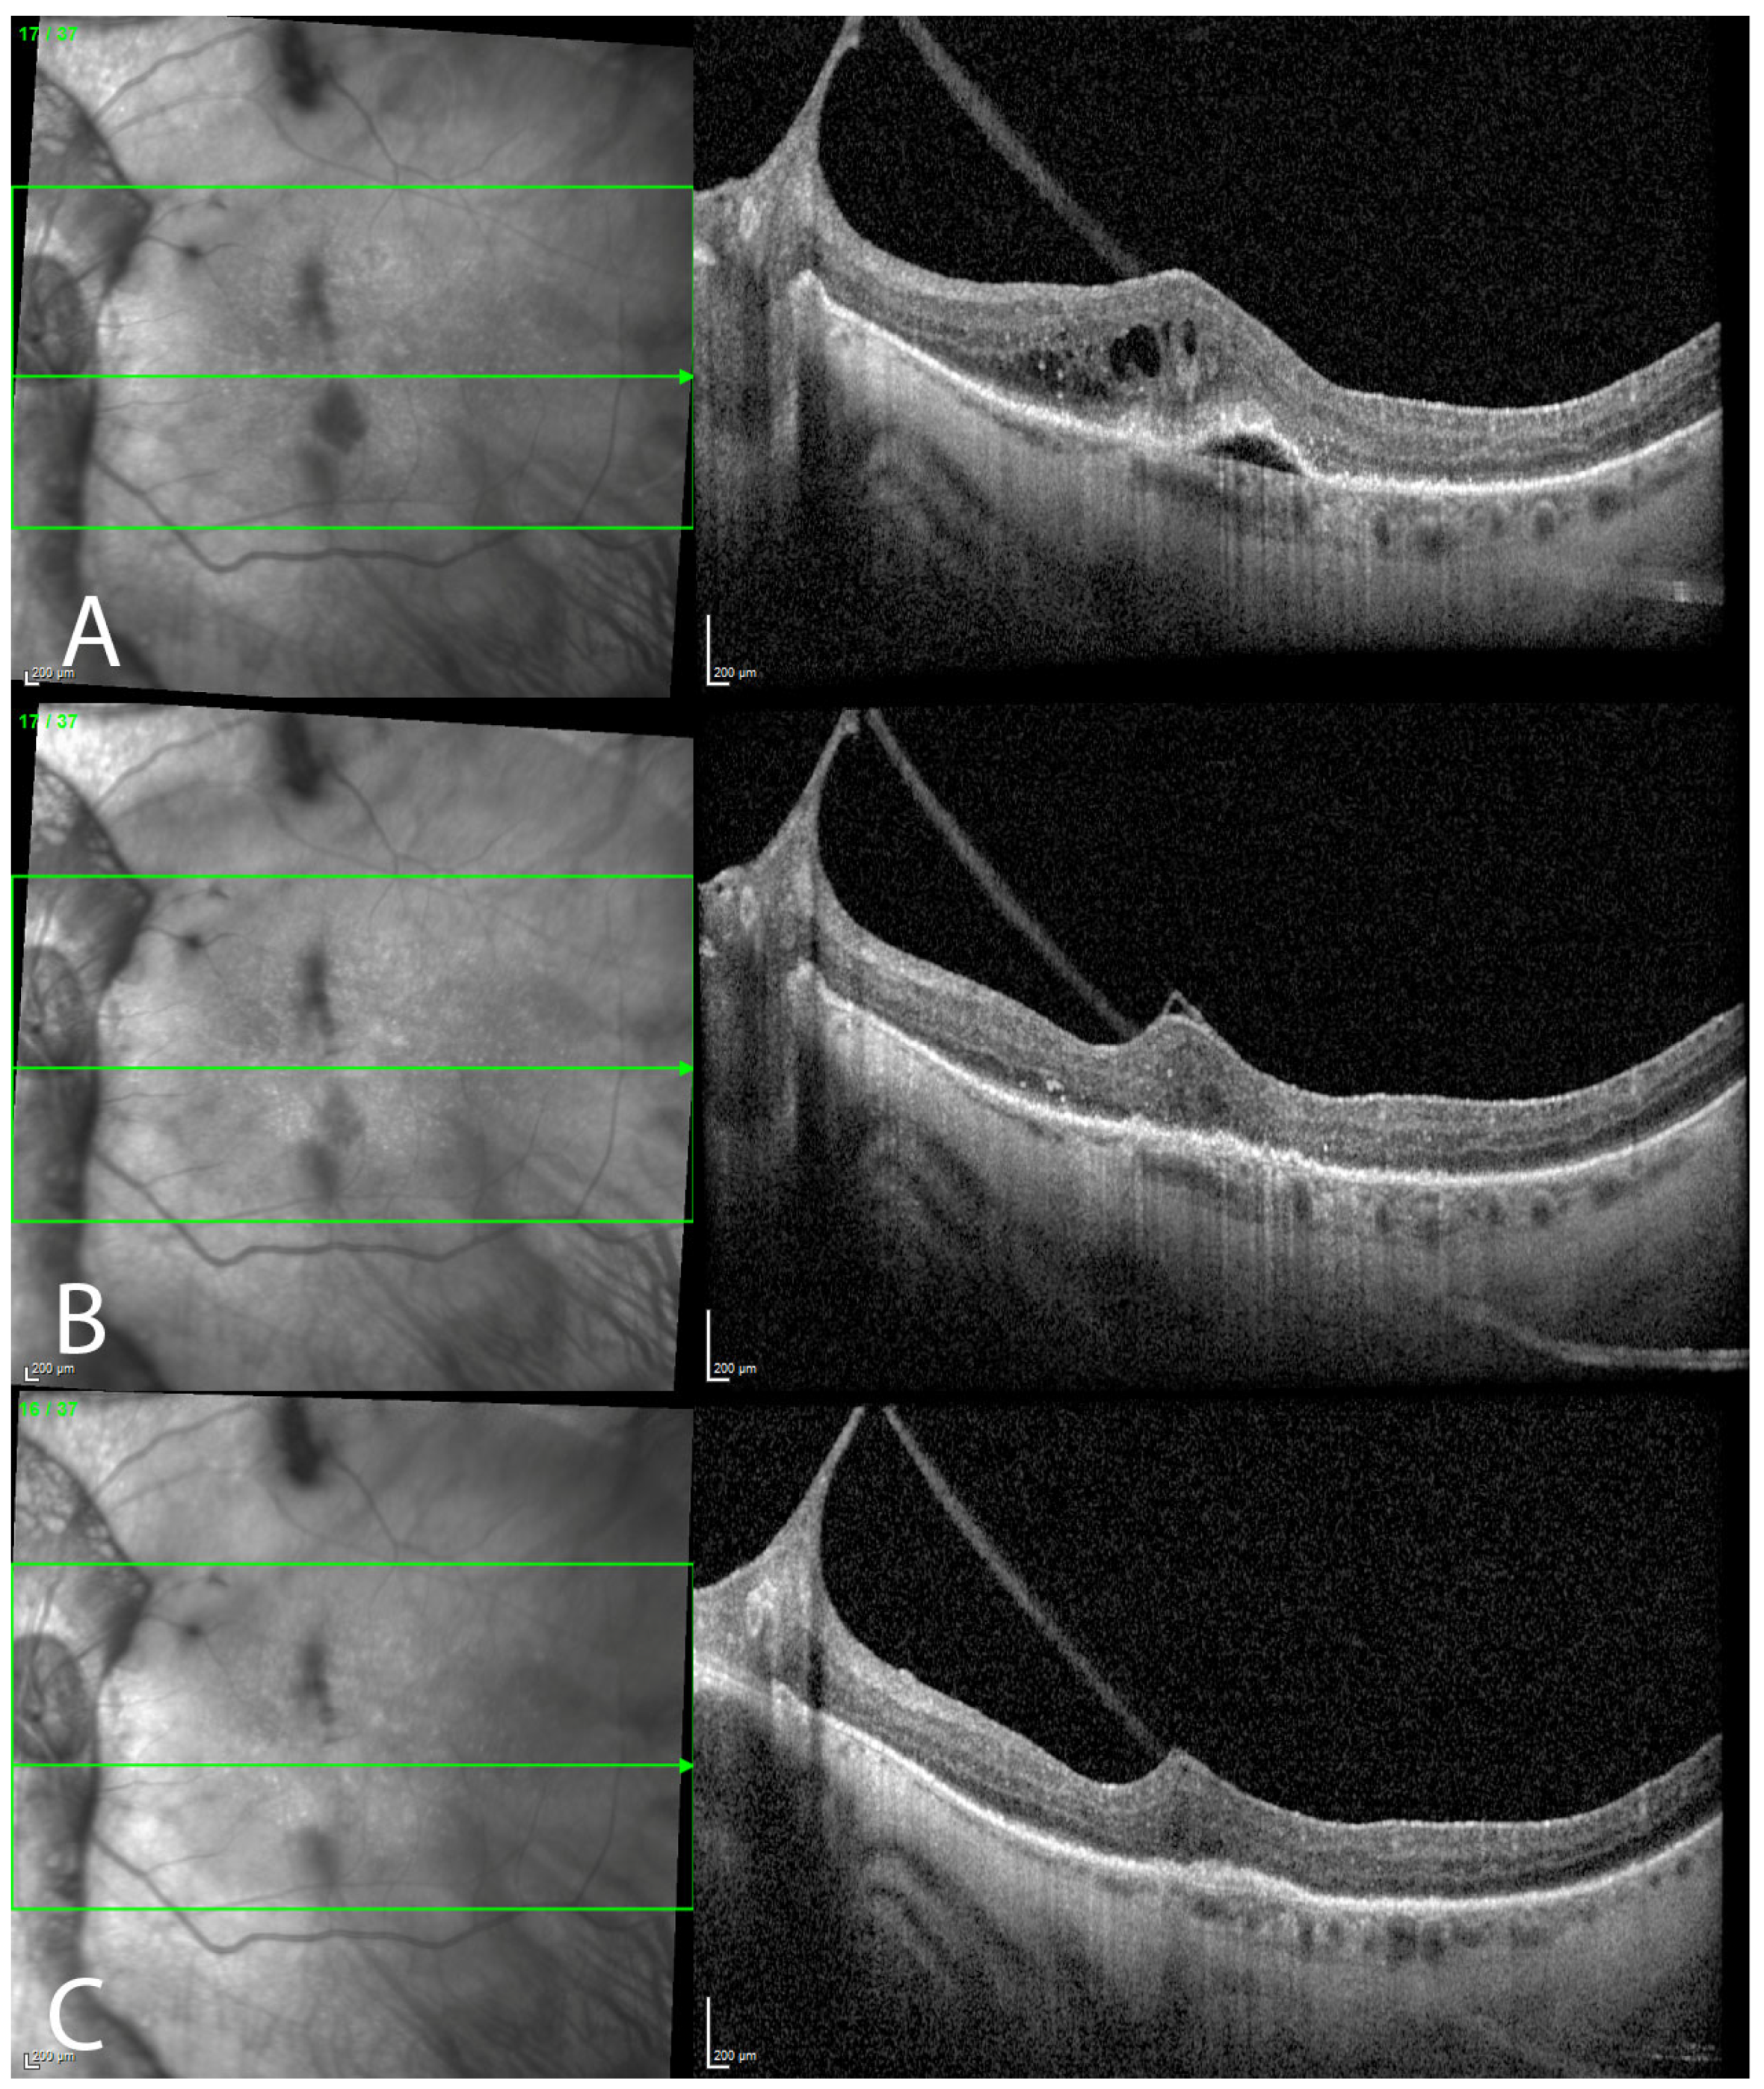

3. Results